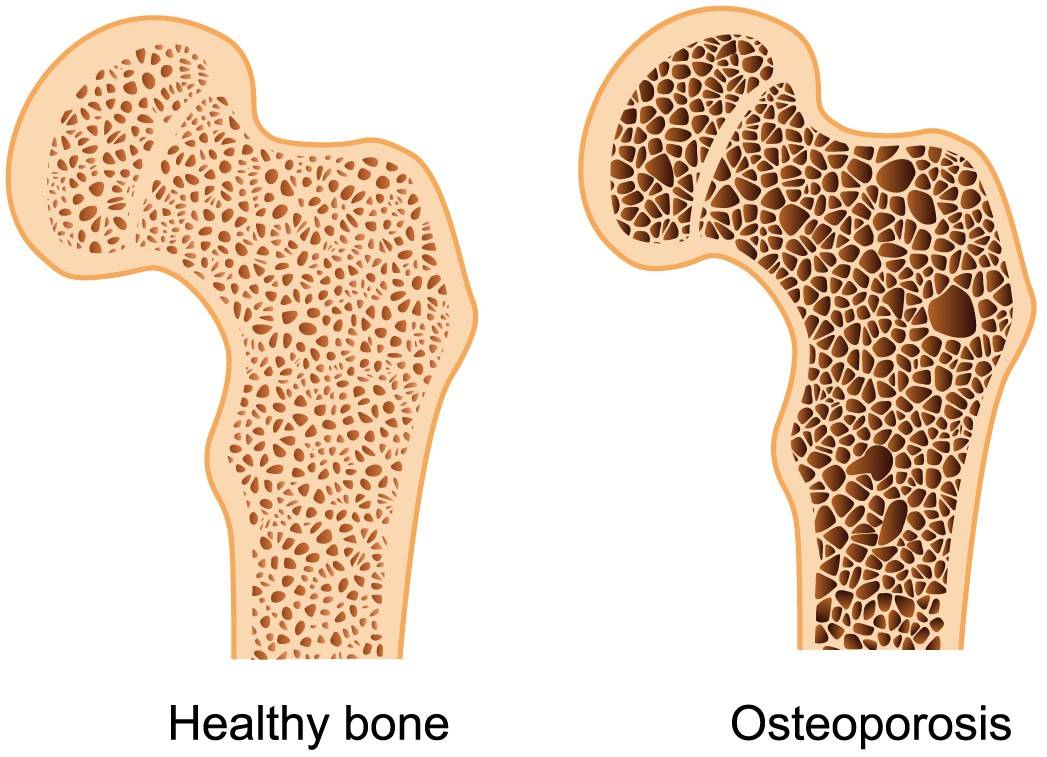

BONE DENSITY

MEASUREMENT OF THE DENSITY/HARDNESS OF YOUR SKELETAL SYSTEM ASSESSING FOR OSTEOPOROSIS/OSTEOPENIA.